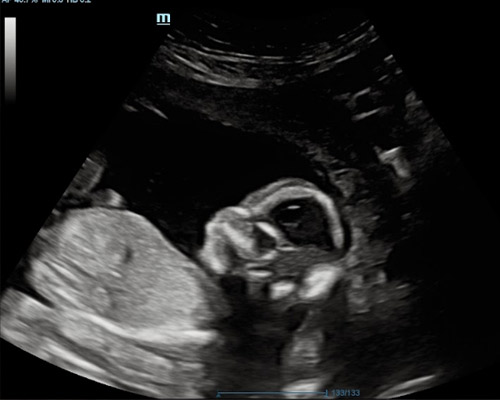

A reassurance scan is an ultrasound carried out during pregnancy to check how your baby is doing and to offer extra peace of mind between routine appointments. Many parents choose this type of scan when they want a closer look at their baby’s progress or simply wish to see them again.

During the scan, the sonographer looks at key signs of development such as heartbeat, movement, overall activity and positioning within the womb. This non-invasive method provides a clear picture of how things are progressing and can help ease common worries.

For many families, a reassurance scan near Worksop becomes a reassuring and memorable experience, especially when they can watch their baby moving on the screen.

- Observe your baby’s movements during the scan

- Visual confirmation of the fetal heartbeat

You may be able to see your baby’s movements, heartbeat, position and general activity during the scan.